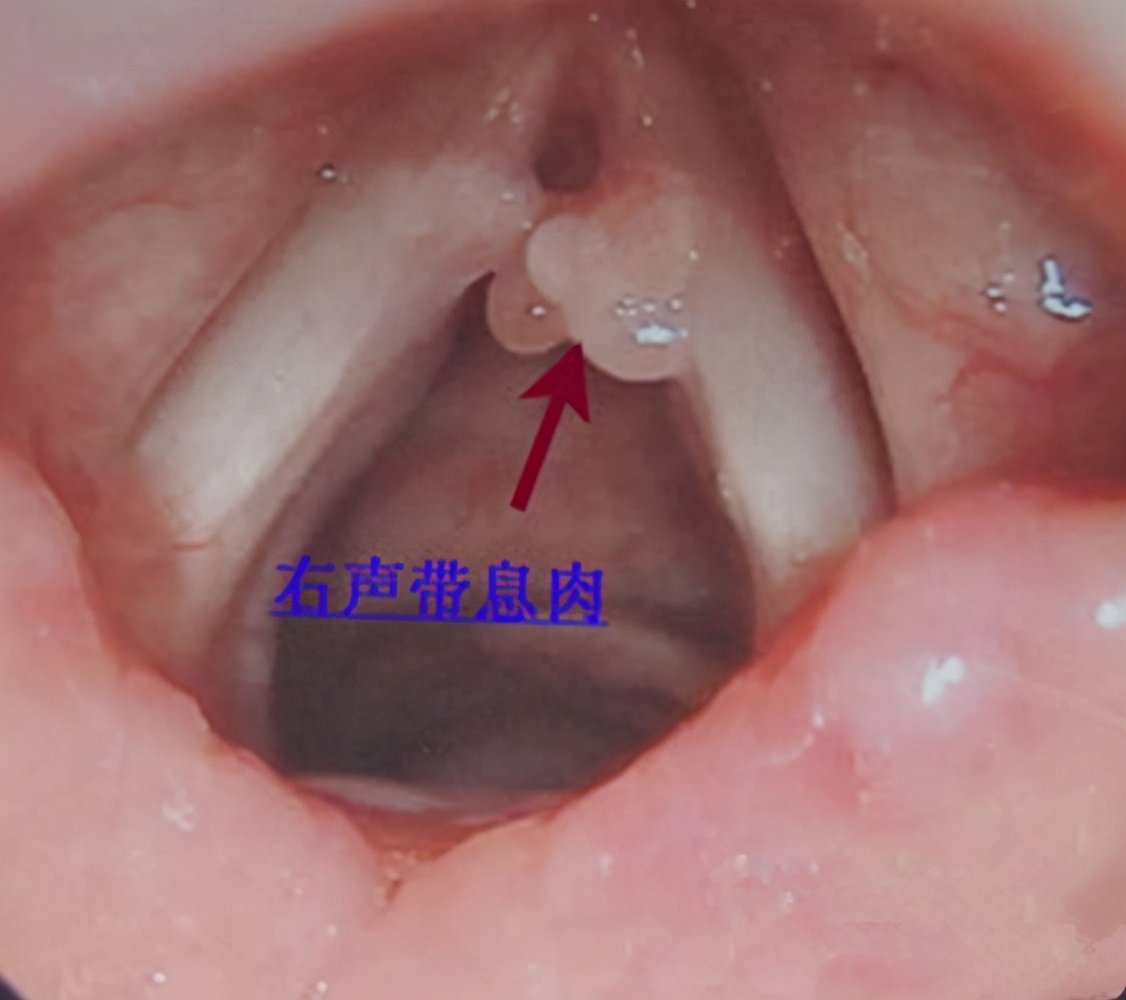

但是过了几天,胡小姐再次试着唱高音的时候依然无法发出声音,并且说话声音也变得嘶哑了,别说上课了,平时讲话都觉得费力难受。这也导致胡小姐根本没办法给学生上课,于是胡小姐来到贵阳铭仁耳鼻喉医院就医,通过给她做咽喉镜发现她的声带一侧有淡红色光滑的赘生物,最后诊断为声带息肉。通过及时切除息肉,胡小姐预后良好,目前已恢复健康。

声带息肉多为一侧单发或多发,颜色呈现灰白色半透明,有时为红色小突起,声带息肉通常伴有声音嘶哑、失音、咽喉干痒、疼痛等症状表现,声带息肉过大可严重阻塞声门,导致发生呼吸困难的危险状况。

产生息肉样组织,声带息肉多发生于声带的前中部边缘,局限性声带息肉因为息肉较小,只表现出声音改变。基底广的声带息肉的声嘶症状较重,有时甚至发生失音的情况,严重的会出现呼吸困难。